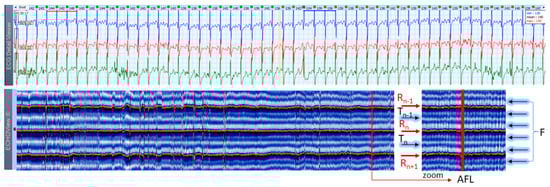

3.6. Atrial Fibrillation and Flutter Cases

AF is the most common arrhythmia among humans (1 of 4 will have at least 1 episode of this arrhythmia in his/her life). This rhythm disorder and the less common AFL are usually not difficult to be recognized in standard 12-lead ECG strips if the ventricular rate is not too high and the fibrillation ‘f’ waves or flutter ‘F’ waves are visible in at least one lead. However, if HR is very high and irregularity of the rhythm, and fibrillations (in AF) or ‘saw-like’ fluctuations of the isoelectric line (in AFL) are not visible, it could be difficult to say what kind of arrhythmia the patient has. In addition, in many patients these arrhythmias are transitory and sought by Holter ECG/event recorders, which records frequently have a lot of artifacts due to physical activities and other factors. In such cases, ECHOView may help to recognize AF/AFL arrhythmias because they have a very characteristic pattern on the color map, as shown in Figure 13, Figure 14 and Figure 15. The notable behavior of AF is the absence of a P-wave band and scattered dots of R-wave peaks (Figure 13 and Figure 14), while AFL has presence of several F-wave bands and stable band of R-wave peaks (Figure 15). Beneficially, these ECHOView maps sufficiently differ from the patterns of other high-rate arrhythmia, such as SINT (Figure 6, Figure 7 and Figure 8), SVA (Figure 9) and PSVT (Figure 10, Figure 11 and Figure 12).

4.3. ECHOView: Summary of the Principles of Imaging

ECHOView modality discloses clearly in a color-coded pattern the presence and morphology of different ECG waves in sequential beat intervals. Thanks to the highly distinctive color map (black-blue-white-orange-red), the ECG waves can be easily discerned and their alignment to the central R-peak can be tracked in long duration ECHOView pages (mean duration of 24.5 min per page). This is especially important for the traditionally difficult recognition of the P-wave, which in all example cases is visible as a blue-white horizontal trace above R-peaks when present in NSR (Figure 4, Figure 5, Figure 9, Figure 10 and Figure 11), SINT (Figure 6, Figure 7 and Figure 8) and PSVT (Figure 10, Figure 11 and Figure 12). Similarly, a series of vertically displaced white traces are recognized for the F-waves in AFL (Figure 15 and Figure 16). On the contrary, a white horizontal P-wave trace is missing in NSVT (Figure 17) and AF (Figure 13, Figure 14 and Figure 16), where f-waves are discerned as randomly located light spots. The presence or absence of the P-wave in SVES and VES beats is difficult to be recognized in compressed ECHOView pages unless the area of the ectopic beat is zoomed as in Figure 4 and Figure 5 (right). Nevertheless, the identification of SVES/VES is possible by observations of the red dots (R-peak) and yellow/orange dots (T-peak) visible as occasional events in the blue horizontal area between Tn−1 and Pn (Figure 4 and Figure 5). Additionally, VES are associated with a change in the QRST waveform compared to NSR beats, which is recognized on the ECHOView color map as a contrasting color change, e.g., in Figure 5 from blue to black (during the negative T-wave of VES). Whereas the inspection of such color changes for single VES beats requires a zoomed ECHOView image (Figure 5), the recognition of NSVT episodes including multiple VES beats seems easier in the compressed ECHOView page (Figure 17). However, our observations of NSVT are limited because these are rare events in our Holter ECG population, observed in only 3 patients with short rushes ≤ 11 beats.

The color-coded ECG amplitudes of sequential beats produce an intuitive trace of different intervals (PnRn, RnTn, Rn−1Rn, RnRn+1, etc.) in a visible image (width × height = 1740 beats × 1500 ms) within one ECHOView page. Without a specific measurement, this visual effect resembles the rendering of one-dimensional time trends of automatically measured ECG intervals. These trends show stable PnRn and RnTn intervals during the NSR part of the examples in Figure 4, Figure 5, Figure 6, Figure 7, Figure 8, Figure 9, Figure 10, Figure 11 and Figure 12. The trends are also informative for the RR-intervals (Rn−1Rn, RnRn+1) on a beat-by-beat basis that is helpful for identifying long-term HR changes in high-rate SINT (Figure 6, Figure 7 and Figure 8) and AFL (Figure 15), as well as rhythm, transitions NSR→ paroxysmal SVA (Figure 9), NSR→PSVT (Figure 10, Figure 11 and Figure 12), NSR→NSVT (Figure 10, Figure 11 and Figure 12), and AF→AFL→ST (Figure 16).